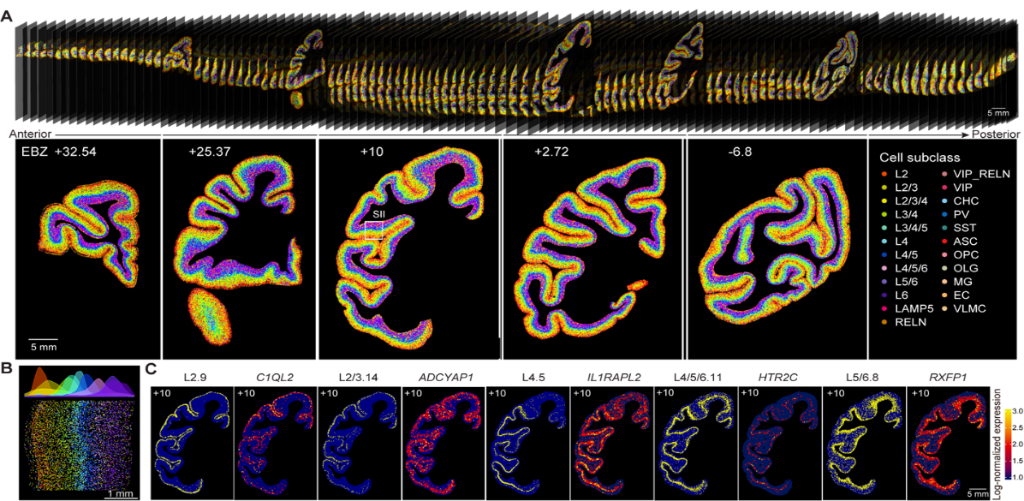

猕猴大脑皮层细胞类型空间分布图谱。(中国科学院脑智卓越中心供图)

“与其他物种相比,灵长类动物有更高的认知和社会能力,有更大的大脑皮层和更多的细胞类型,而猕猴是与人类最接近的模式动物。”中国科学院脑智卓越中心研究组组长李澄宇说,团队利用我国自主研发的超高精度大视场空间转录组测序技术和高通量单细胞核转录组测序技术,获得了世界首套单细胞分辨率的猕猴大脑皮层细胞空间分布图谱。

中国科学院脑智卓越中心全脑介观神经联接图谱研究(单细胞分型)平台主任李超介绍,团队检测了4000多万个皮层细胞,并根据细胞的分子及空间分布规律,将它们分为264种不同的细胞类型。

猕猴大脑皮层细胞类型及基因表达数据库。(中国科学院脑智卓越中心供图)

研究表明,大量兴奋性神经元、抑制性神经元以及非神经元细胞在大脑皮层中的分布,有明显的各层面及各脑区特异性。更有趣的是,相同层级的脑区,往往细胞类型组成类似。

另外,通过与公开发表的人脑和鼠脑的单细胞数据进行跨物种比较,团队发现了灵长类特有的、分布于第四层的兴奋性神经元细胞,这些细胞高度表达与人类疾病相关的基因。